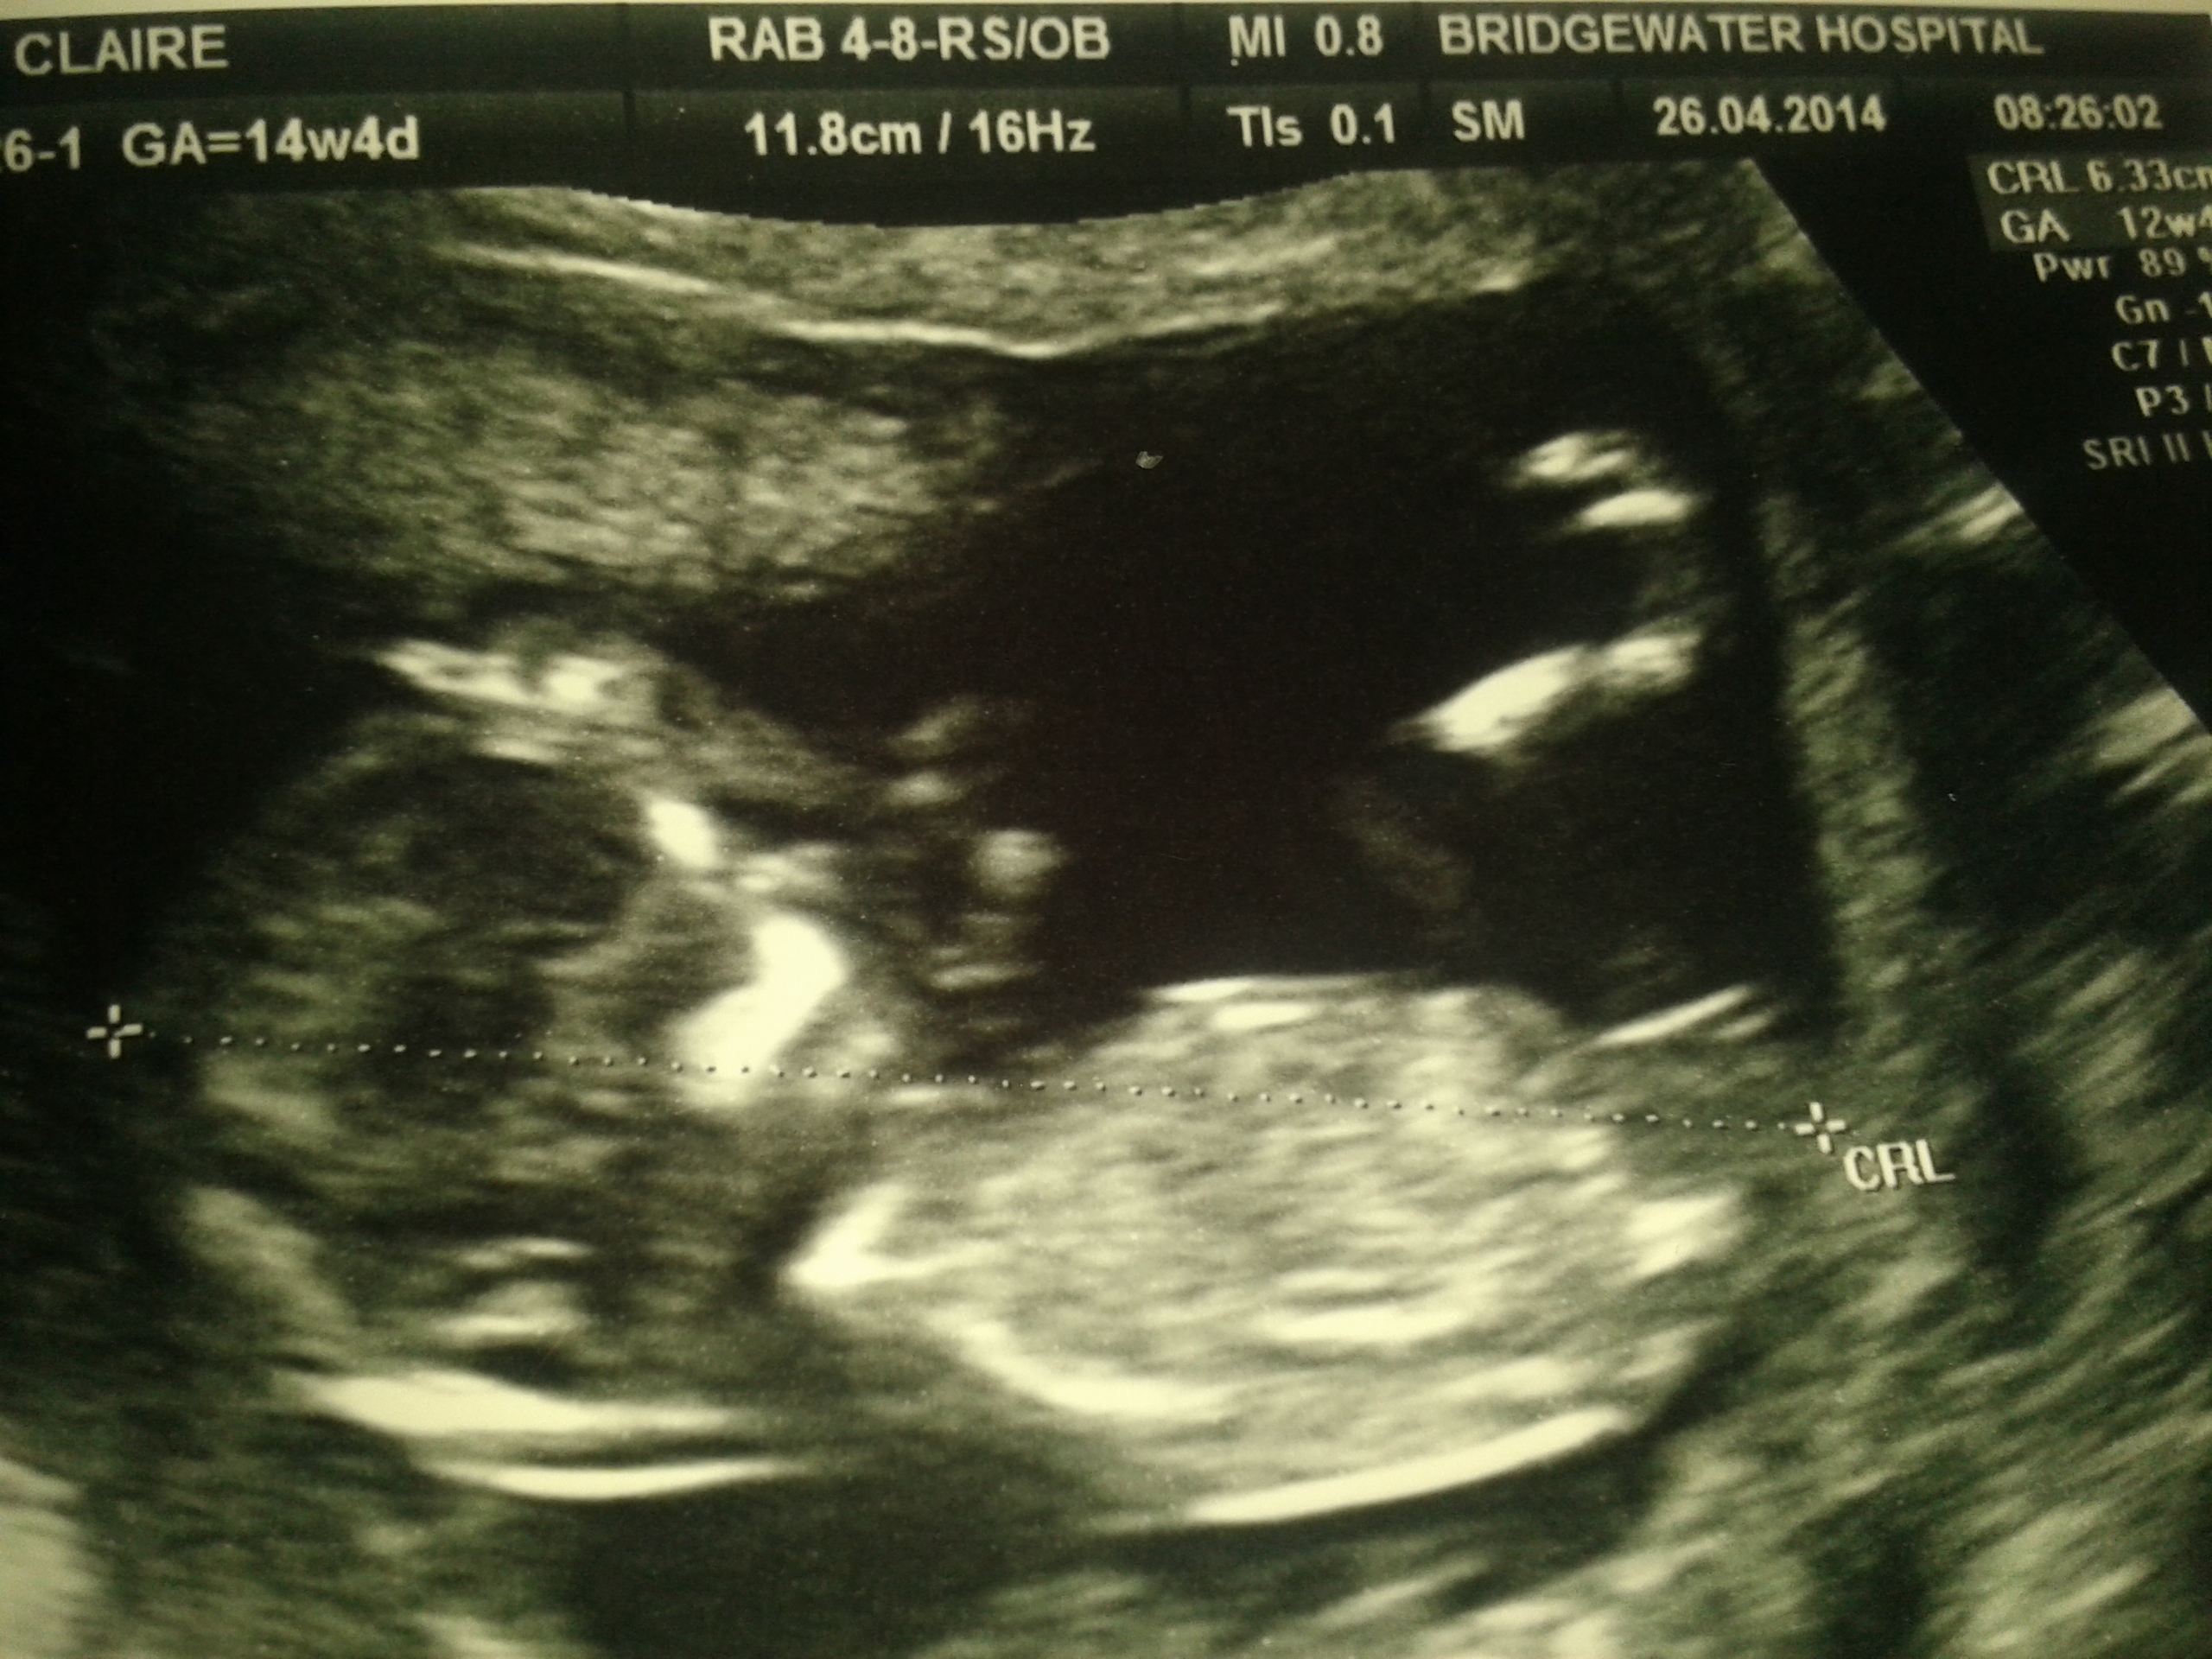

hope pics are ok and show the nub i had no idea !!!!

Guessing boy based on top photo.

girl

Hard to tell, but I guess girl.

I see on one of the pics that you were 14 wks in these? In that case I'm thinking girl bc boy would be very more angled at that gestation.

definitely looks girly

This is a tough one... I give it a slight girl lean but I wouldn't be surprised to hear this one is a boy.

I'd guess girl.